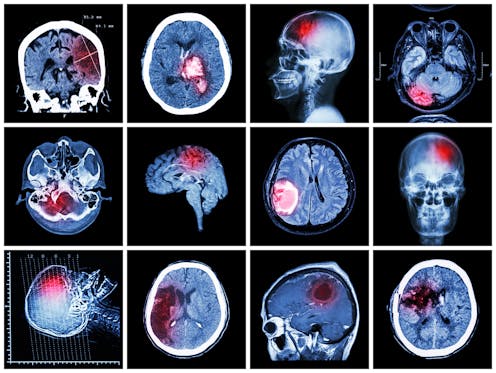

Traumatic brain injury refers to damage of the brain caused by an external force, such as from a traffic accident, fall or assault (such as a coward punch). This leads to bruising, bleeding, and tearing of brain tissue.

Traumatic brain injuries fall on a spectrum of severity, with the initial loss of consciousness and duration of confusion (known as post-traumatic amnesia) used to classify brain injuries as mild, moderate, or severe. Most traumatic brain injuries (approximately 80%) are mild.

Dementia is caused by a progressive build-up of proteins in the brain, which ultimately causes brain cells to die.

There are several types of dementia, including Alzheimer’s disease, dementia with Lewy bodies, vascular dementia, and frontotemporal dementia.

Each dementia type is caused by a different type of protein, and affects different parts of the brain, leading to diverse symptoms. It’s not known what causes this abnormal build-up of proteins in the brain.